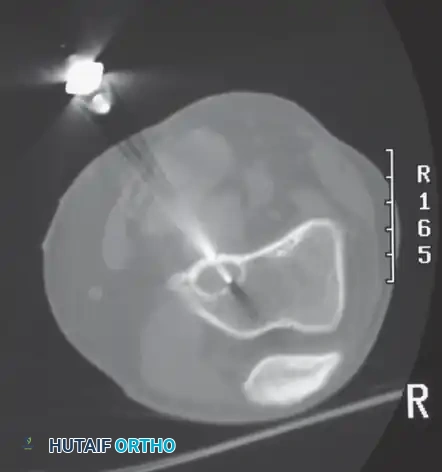

C: Intraoperative view. Because the clinical and radiographic picture overwhelmingly pointed to a low-grade chondrosarcoma (which is chemo/radio-resistant), a primary en bloc resection of the proximal fibula was performed without a prior biopsy. This strategic decision prevented biopsy tract contamination, allowing the surgeon to achieve wide margins while safely dissecting and preserving the common peroneal nerve (arrow).